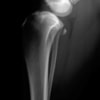

術前正面像

術前のTPAは左後肢33.1°右後肢26.8°でしたがTPLO実施により左後肢5.5°右後肢12°に矯正されました。

手術前後のTPA(脛骨高平部の角度)を測定しています。

約29°から約10°へ矯正されています。